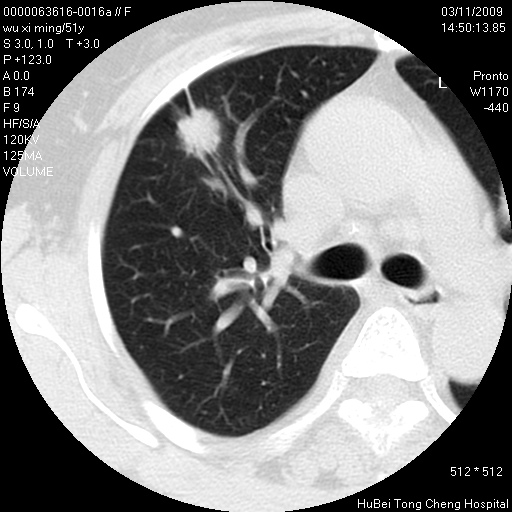

患者 女,51岁。因“胆囊炎,胆囊结石”,行常规术前胸部x线检查发现:右上肺结节病灶,建议行进一步检查。患者无咳嗽、咳痰及咯血等呼吸道症状,近期出现背部疼痛不适。

胸部ct轴位平扫(层厚10mm,螺距1.5,重建间隔10mm;部分层面:层厚3mm,螺距1.0,重建间隔3mm),图像如下:

1、周围型肺癌。(毛刺正、血管束集征,分叶。)

集束征,胸膜牽拉征,毛刺,淺分葉高度提示ca.